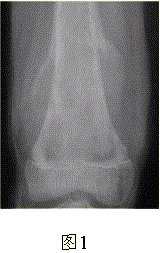

问题 患者男,16岁,左大腿下部疼痛伴肿胀2个月,逐渐加重。自感左膝上方胀痛,尤以夜间为著,伴行走困难。既往史及家族史无特殊。查体:左大腿下部明显肿胀,皮温较对侧升高。碱性磷酸酶明显增高。股骨平片及MRI见下图。 关于此病变的定位,正确的是

选项 A.病变主体位于左股骨下端骨骺,累及干骺端 B.病变主体位于左股骨下端干骺端,累及骨骺 C.病变主体位于左股骨远侧骨端 D.病变主体位于左股骨下端周围软组织,骨质受累 E.病变主体位于骨髓质,皮质受累 F.病变主体位于骨皮质,髓质受累

答案 BE